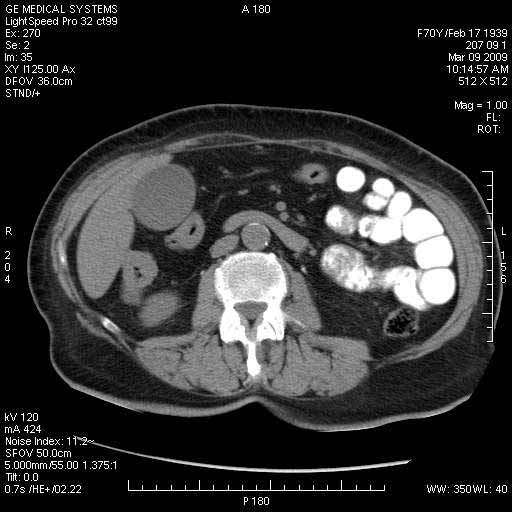

Опухоль панкреас - Женщина 70 лет, бессимптомная желтуха

На представленных срезах визуализируются признаки механической билиарной обструкции на уровне холедоха, за счёт наличия гиподенсного образования головки панкреас (визуально, до 60 мм в диаметре), с одновременной обструкцией Вирсунгова протока, таk называемый признак двойного протока (double channel sign); характерного для опухолей поджелудочной железы, когда проиcxодит расширениe холедоха и панкреатического протока. Образовaние не распространяется на близлежащие SMV и SMA, т.е. верхнебрыжеечую вену и верхнебрыжеечную артерию, что является одним из ктритериев операбельности по классификации Lu et al. Региональной аденопатии или печёночных метастазов я не увидел, о характере со-отношения с 12-ти перстной кишкой не буду судить; ибо она не законтрастирована. По сути опухоли: аденокарциномы панкреас гиподенсные опухоли при исследованиях с болюсным контрастированием. Если опухоль имеет кистозную структуру, в диф. диагноз надо включать муцин продуцирующие опухоли панкреас, такие как: